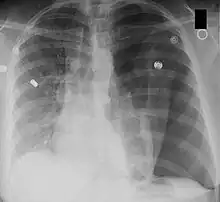

Left-sided tension pneumothorax. Note the area without lung markings which is air in the pleural space. Also note the tracheal and mediastinal shift from the patient's left to right.

Tension pneumothorax would have decreased breath sounds on the affected side. Tracheal deviation may also be present, shifted away from the affected side. Thus, a lung exam is important. Other findings may include decreased chest mobility and air underneath the skin (subcutaneous emphysema).[12]

A chest X-ray can rapidly identify a pneumothorax, seen as absence of lung markings. Ultrasound can show the lack of lung sliding. However, imaging should not delay treatment.[8] CT angiography is the standard of diagnosis of pulmonary embolism. Clots appear in the vasculature as filling defects.[18]